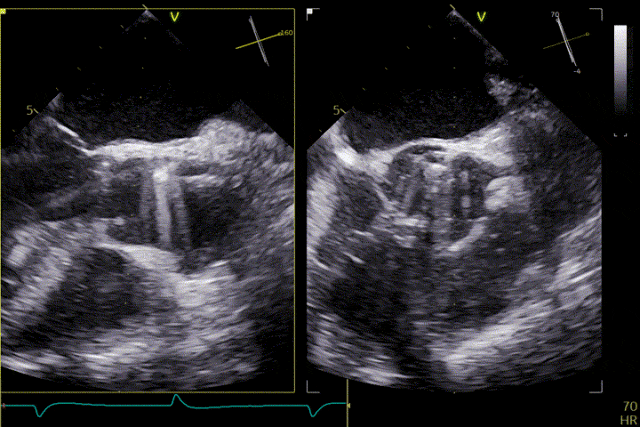

Under echocardiographic guidance, the surgical team efficiently and precisely completed valve positioning, deployment, and functional assessment. The procedure proceeded smoothly: engagement of the graspers into the aortic sinuses and positioning were accomplished in one continuous step. The release and anchoring positions of the three graspers were fully consistent with the preoperative assessment, and device manipulation time was approximately 5 minutes. Intraoperative echocardiography showed no paravalvular leak, and hemodynamic parameters remained stable throughout. The procedure was completed successfully without complications.

Valve release

The patient's severe aortic regurgitation was successfully corrected. Postoperatively, there was no residual regurgitation or paravalvular leak. Postoperative echocardiography showed that the bioprosthetic valve had normal opening and closing function, with a mean transvalvular pressure gradient of 2 mmHg and normal flow velocity. The patient demonstrated good recovery, with a significant improvement in cardiac function compared with the preoperative status.